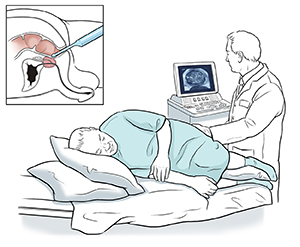

Your prostate gland is in front of your rectum. For TRUS, a special handheld probe (called a transducer) is put into your rectum to see your prostate. During this test, tissue samples (called a biopsy) may be taken out with a thin needle. A biopsy is used to diagnose cancer. This may be done if other tests, like a prostate-specific antigen (PSA) or a digital rectal exam (DRE), are abnormal.

TRUS is done by a specially trained technologist called a sonographer. It takes about 15 to 30 minutes. It might take longer if a biopsy is done during the TRUS by your healthcare provider (urologist). TRUS and biopsy can be done at your provider's office or an outpatient clinic.

You'll be asked to change into a hospital gown. You'll then lie on your side on an exam table, with your knees bent toward your chest. You will be awake during the test.

The test is done with a handheld probe. This is a short, slender rod about the size of your finger. It has a sterile, disposable cover on it. It's covered (lubricated) with gel. It's gently put inside your rectum.

Sound waves are sent into the probe and through the wall of your rectum. They bounce off your prostate. A computer uses them to form an image of the gland and nearby tissues. It can help find abnormal tissue in the prostate that may be cancer. This helps the provider know where to guide the needle to take out small samples of tissue for a biopsy.